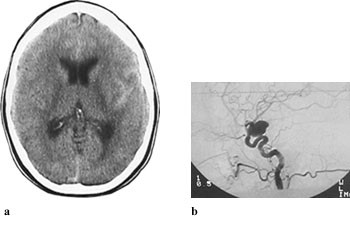

Subaraknoidalblødning ble påvist ved CT-undersøkelse hos 64 av 70 pasienter (91 %). Blod ble hyppigst påvist i basale cisterner (75 %), i fissura Sylvii (73 %) og i cerebrale kortikale sulci (67 %) (tab 1, fig 1 – 5). Funn forenlig med økt intrakranialt trykk (utvidet ventrikkelsystem, spesielt sideventriklenes temporalhorn og/eller overskyvning av midtlinjestrukturer, endret form av basale cisterner, utvisket overflaterelieff og/eller periventrikulært ødem) ble påvist hos 26 pasienter (41 %).

Opplysninger vedrørende cerebral angiografi forelå hos 64 av 70 pasienter med subaraknoidalblødning. Av disse hadde ti (16 %) normalt funn. Til sammen 63 aneurismer ble påvist hos 52 pasienter (81 %). Intracerebral arteriovenøs malformasjon ble påvist hos to pasienter. Hos seks pasienter ble det gjort samtidig funn av henholdsvis fire (n = 2), tre (n = 1) og to (n = 3) aneurismer ved samme undersøkelse. Aneurismer ble hyppigst påvist på a. cerebri media, a. communicans anterior og a. carotis interna (tab 2). Påvisning av blod i subaraknoidalrommet kunne gi indikasjon på lokalisering av aneurismet (tab 2, fig 2, fig 4). Prediksjon for påvisning av lokalisasjon av blødende aneurisme var kun meget god for aneurismer på a. cerebri media, hvor 12 av 13 aneurismer ble lokalisert korrekt. Det var dårligere prediksjon for aneurismer lokalisert til a. communicans anterior og a. carotis interna, med henholdsvis 11 av 18 og fire av ti aneurismer riktig lokalisert. Angiografi var utført hos åtte av ti pasienter med blod i septum pellucidum, og hos samtlige ble det påvist aneurisme på a. communicans anterior (fig 4). For de andre lokalisasjonene var det få observasjoner og lav treffsikkerhet.